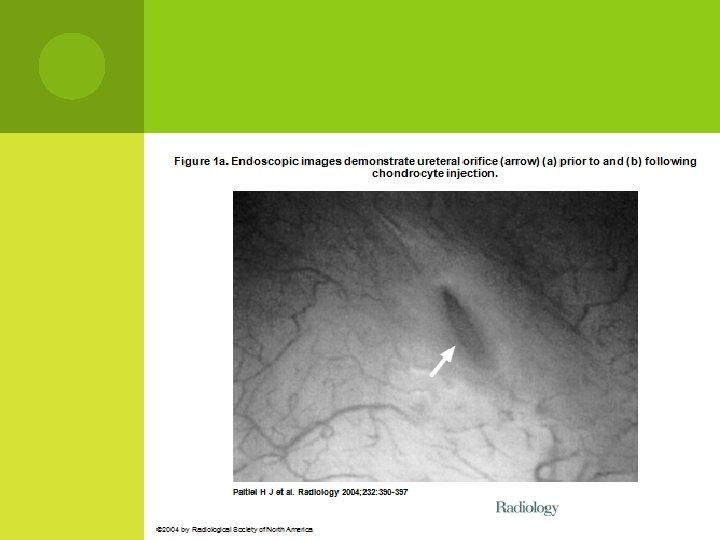

Figure 1 b. Endoscopic images demonstrate ureteral orifice (arrow) (a) prior to and (b) following chondrocyte injection. Paltiel H J et al. Radiology 2004; 232: 390 -397 © 2004 by Radiological Society of North America